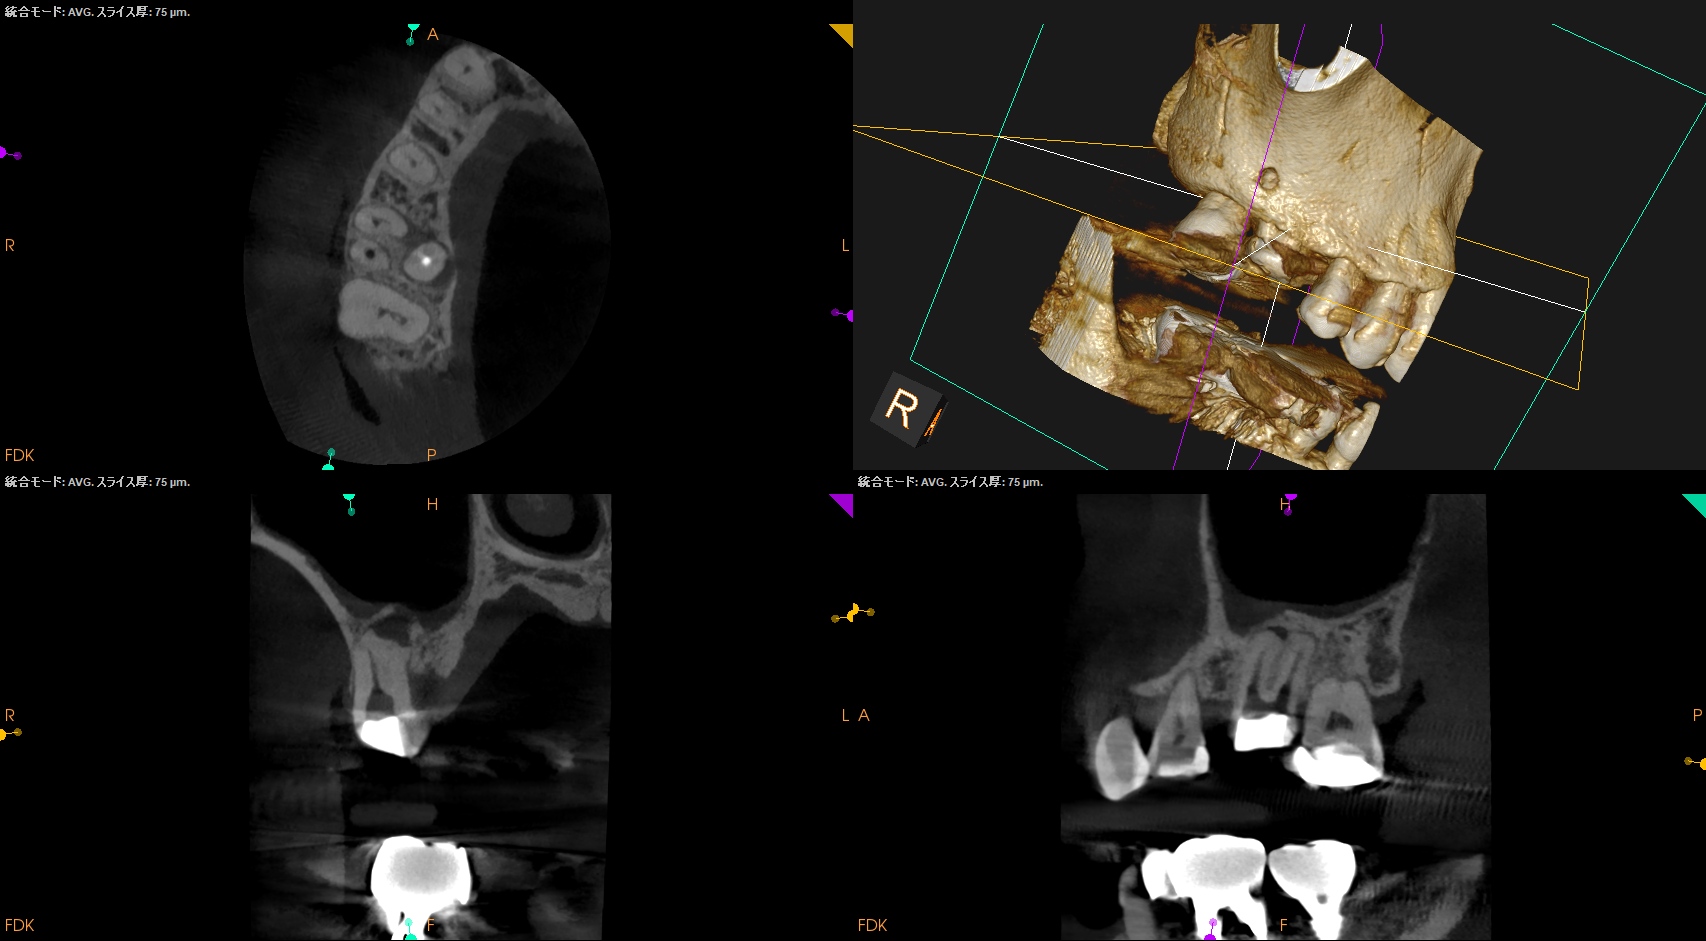

術後にPA, CBCTを撮影した。

MB

DB

B

問題はないだろう。

#3 MB,DB Apicoectomy(2025.8.25)

MBからOsteotomyした。

MBを3mm Root resectionした。

切断後にメチレンブルーで染色しRetroprepし, Retrofillした。

次がDBである。

Osteotomyし、当該部位をRetroprep, Retrofillした。